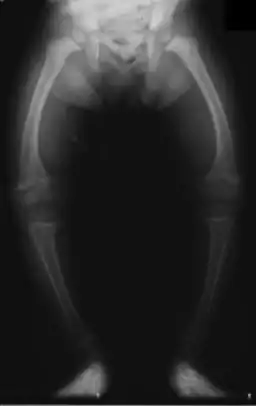

| X-ray of a two-year-old with rickets, with a marked bowing of the femurs and decreased bone density | |

Young children may have bowed legs and thickened ankles and wrists;[13] older children may have knock knees.[10] Spinal curvatures of kyphoscoliosis or lumbar lordosis may be present. The pelvic bones may be deformed. A condition known as rachitic rosary can result as the thickening caused by nodules forming on the costochondral joints. This appears as a visible bump in the middle of each rib in a line on each side of the body. This somewhat resembles a rosary, giving rise to its name. The deformity of a pigeon chest[10] may result in the presence of Harrison's groove.

An X-ray or radiograph of an advanced sufferer from rickets tends to present in a classic way: the bowed legs (outward curve of long bone of the legs) and a deformed chest. Changes in the skull also occur causing a distinctive "square headed" appearance known as "caput quadratum".[14] These deformities persist into adult life if not treated. Long-term consequences include permanent curvatures or disfiguration of the long bones, and a curved back.[15]

- Radiography typically show widening of the zones of provisional calcification of the metaphyses secondary to unmineralized osteoid. Cupping, fraying, and splaying of metaphyses typically appears with growth and continued weight bearing.[36] These changes are seen predominantly at sites of rapid growth, including the proximal humerus, distal radius, distal femur and both the proximal and the distal tibia. Therefore, a skeletal survey for rickets can be accomplished with anteroposterior radiographs of the knees, wrists, and ankles.[36]